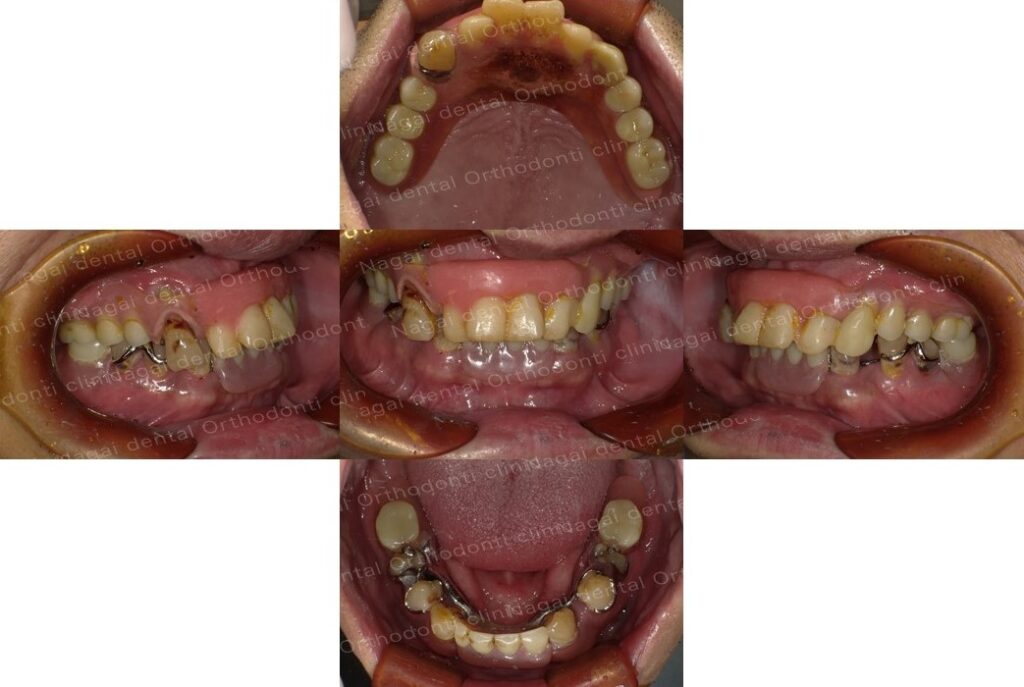

【口腔内の詳細変化】

▲部分欠損や咬合の乱れに伴う咀嚼能率低下の改善を図りました

▲部分欠損や咬合の乱れに伴う咀嚼能率低下の改善を図りました

▲インプラントによる固定式補綴物で、全体的な咬合の再構築を目指しました

| 治療内容 | 上下顎:オールオンフォー(チタンフレームジルコニアセラミック仕上げ) |

|---|---|

| 年齢/性別 | 50代/男性 |

| 背景 | 左側での咀嚼困難や、年々広がる歯間の隙間、および咀嚼時の不具合を主訴に来院されました。過去に部分入れ歯の適応を受けたものの、装着時の痛みから使用を中断されており、取り外し式の入れ歯以外の治療法を希望されていました。事前の咀嚼能率検査でも数値の低下が認められ、速やかな機能回復が求められる状態でした。 |

| 治療期間 | 約7か月(通院12回) |

| 費用 | 6,600,000円(税込)(片顎 3,300,000円×2) |

| リスク/副作用 | インプラント手術は、ご高齢の方や全身状態(持病など)によっては適応とならない場合があります。また、術後の口腔清掃を怠ると天然歯の歯周病に似たインプラント周囲炎が起こる可能性があるため、日々のセルフケアと定期的なメンテナンスが必要です。 |